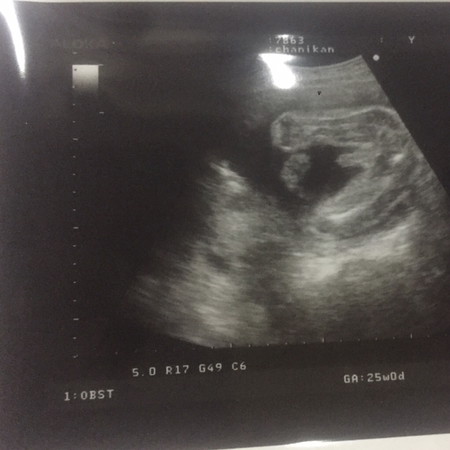

หูยยยยแม่ๆๆๆๆๆ อ้าซ่าขนาดนี้ เดาไม่ยากเลยคร่า

ไม่ต้องบอกหรอกค่ะจู๋น้อยโผล่ขนาดนั้นอ่ะแม่😂

ผู้หญิงค่ะ ที่เห็นเป็นยวงนั่นสายสะดือนะคะ

แหลมมากจ้ะแม่ แหลมมากกกกก จุ๊ดจู๋ชัวร์

👶🏻ผช ค่ะชัดมากเลยค่ะแม่ ยินดีด้วยค่ะ☺️

จู๋ชัดเจนเลยจร้าแม่ ยินดีด้วยค่ะ

งูมาแล้วแม่่่่ ยินดีด้วยค่าา

ผู้ชายค่ะแม่ ยินดีด้วยค่ะ🎉🎉